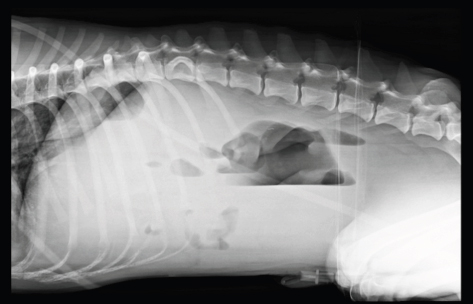

Interestingly, in one case diagnosed without mechanical gastrointestinal ileus, all the reviewers classified it wrongly as mechanical ileus when evaluating the VB views and correctly with only the HB view (Fig. 1).

Fig. 1. (A) Right lateral; (B) ventrodorsal; (C) left lateral; and (D) left-to-right lateral HB views of the abdomen of a dog presented with acute vomiting. In this case, the patient was correctly diagnosed as without mechanical ileus with the HB view and incorrectly diagnosed as mechanical ileus with the VB view by all reviewers. Abdominal ultrasound was unremarkable.

Fig. 3. Example of crowding organs at the ventral aspect of the abdomen in a left-to-right lateral HB view. Evaluation of the ventral abdomen is challenging due to presence of fluid/soft tissue-filled intestines and concurrent peritoneal effusion.